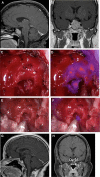

Results: Nine adenomas overexpressed FRα and fluoresced with a NIR SBR of 3.2 ± 0.52, whereas the 5 non-FRα-overexpressing adenomas fluoresced with an SBR of 1.5 ± 0.21. Linear regression demonstrated a significant correlation between intraoperative SBR and the FRα expression (P-value < .001). Analysis of 14 margin samples revealed that the surgeon's impression of the tissue had 83% sensitivity, 100% specificity, 100% positive predictive value, and 89% negative predictive value, while NIR fluorescence had 100% for all values. NIR fluorescence accurately predicted postoperative MRI results in 78% of FRα-overexpressing patients.

Conclusion: Preoperative injection of folate-tagged NIR dye provides strong signal and visualization of NF pituitary adenomas. It is 100% sensitive and specific for detecting margin neoplasm and can predict postoperative MRI findings. Our results suggest that NIR fluorescence may be superior to white-light visualization alone and may improve resection rates in NF pituitary adenomas.